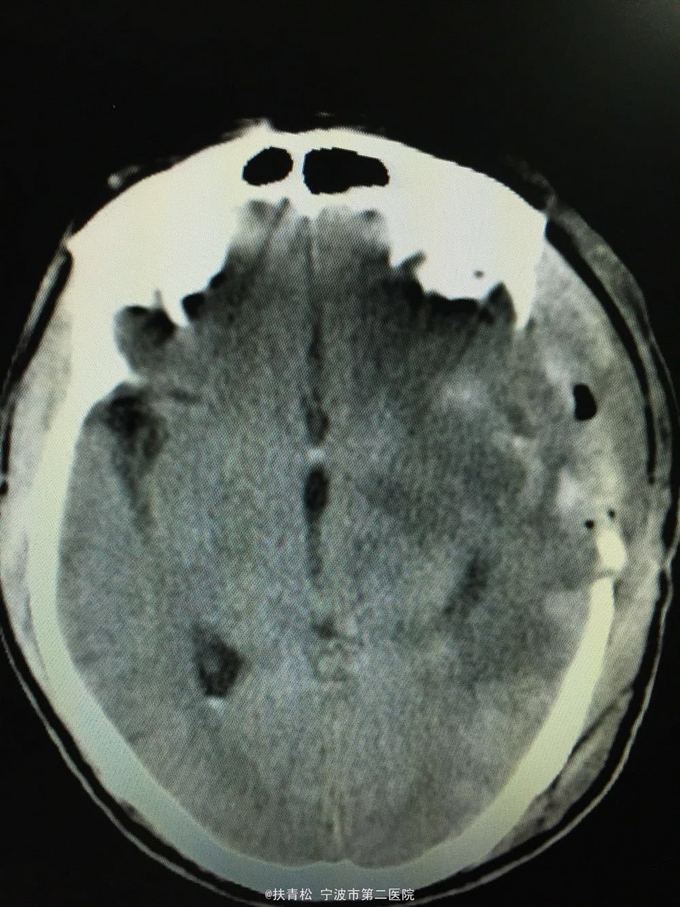

脑胶质瘤

左颞叶胶质瘤

头痛三月余,复发加重一月

行左颞叶胶质瘤切除术